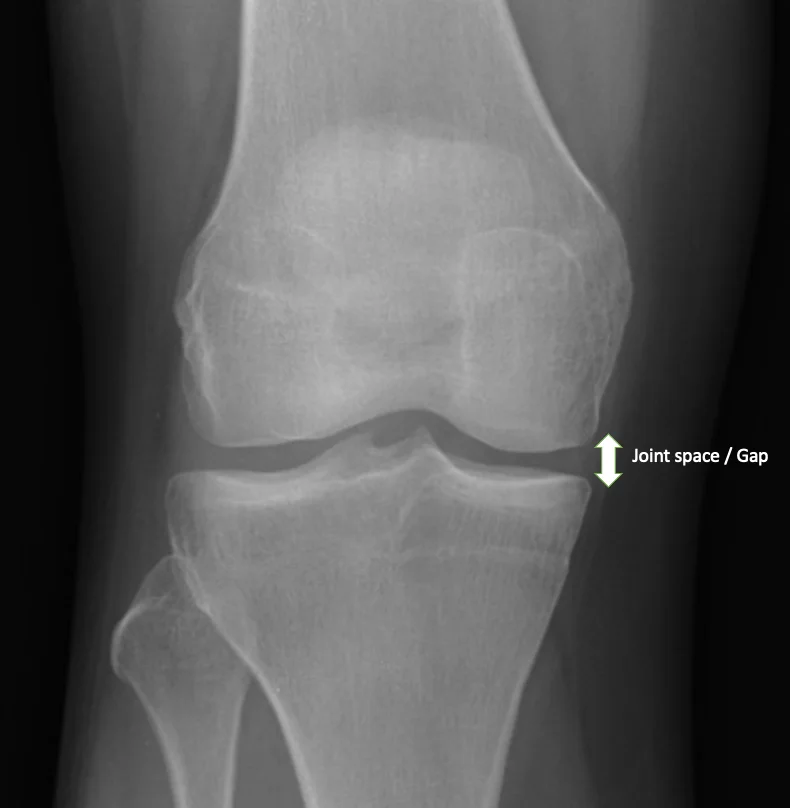

Osteoarthritis

The most common cause of knee pain. In osteoarthritis, the cartilage that cushions the bones wears away, causing:

Orthopaedic surgeon will assess: